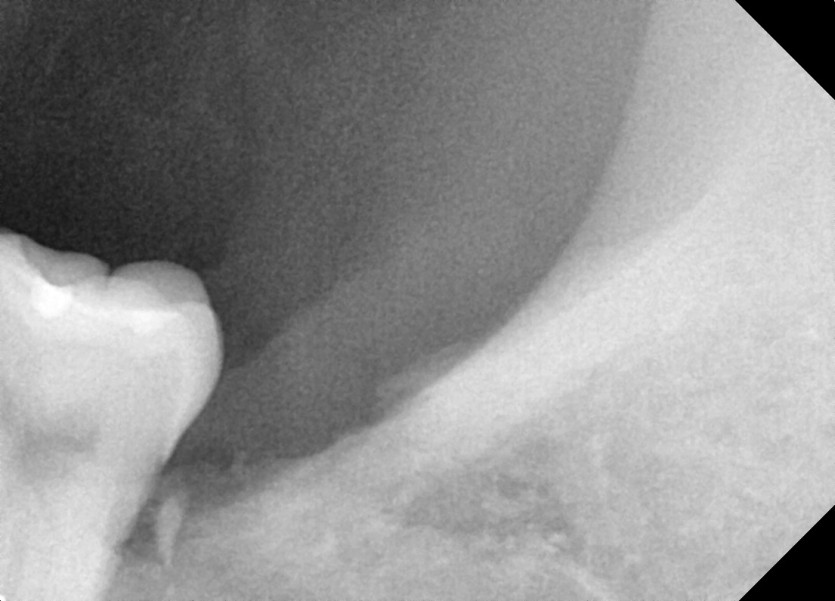

#38 사랑니 발치

구강 외과 전문의가 당일 발치했습니다.